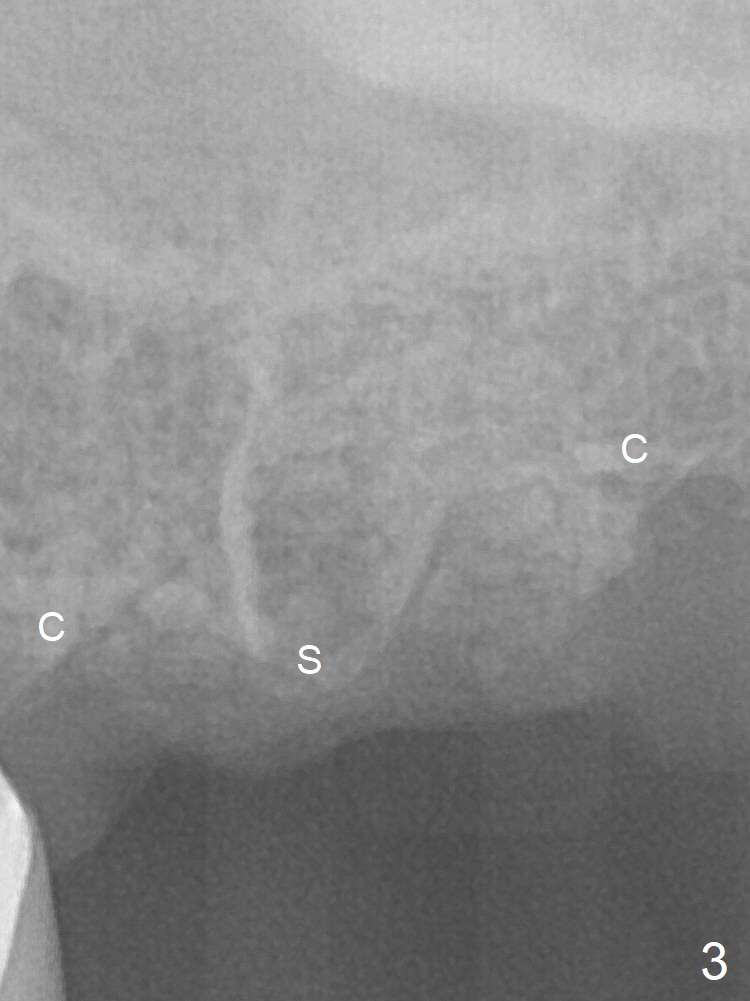

Septum Lower Than Crests

A 53-year-old man requests extraction of the tooth #14 (Fig.1) with pathology mainly around the distobuccal root. It appears that the septum (Fig.2 S) is lower than the crests (C), particularly distally, which is consistent clinically. After placement of Vanilla bone in the thin sockets (relatively large septum, Fig.3), collagen plug and sutures keep the bone graft in place (Fig.4).